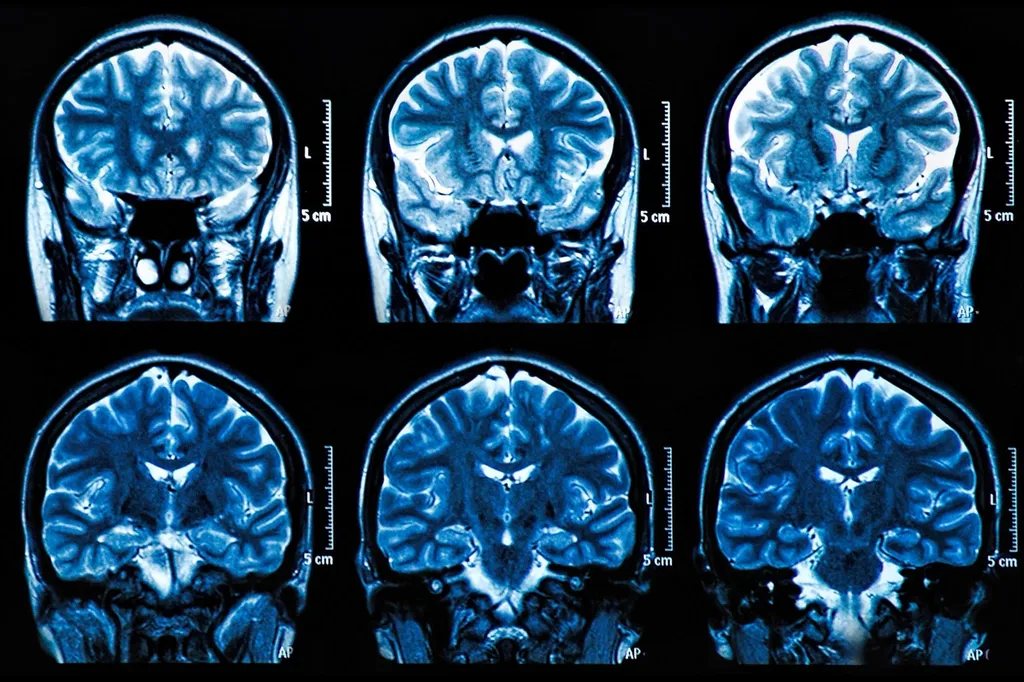

MRI Brain Scan Neuroscience Images

“目前,診斷阿爾茨海默病需要神經(jīng)成像,”皮特大學(xué)精神病學(xué)助理教授、資深作者Thomas Karikari博士說(shuō)?!斑@些檢查很昂貴,需要很長(zhǎng)時(shí)間來(lái)安排,即使在美國(guó),許多患者也無(wú)法使用核磁共振成像和PET掃描儀??稍L問(wèn)性是一個(gè)主要問(wèn)題?!?/p>